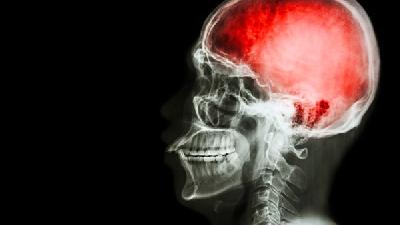

很多家長都擔心一個問題就是腦癱疾病會不會傳染呢?我們知道大多數(shù)的腦癱都是先天性的,或者是出生時因嚴重缺氧所導致。那么可以肯定的說腦癱疾病不是傳染性的疾病,也不會通過接觸傳染給另一個人,所以家長要鼓勵患兒與社會人群在一起。腦癱病傳人嗎?還會不會遺傳呢那么下面我們就一起來看下腦癱病傳人嗎?還會不會遺傳呢?

隨著醫(yī)學界的飛速發(fā)展,腦性癱瘓已不再是不治之癥,康復率也逐年上升。但是問題又隨之出現(xiàn)了,就是小兒腦癱是否會遺傳和傳染?面對這一難題,家長們又開始擔心起來了。

首先腦性癱瘓不會傳染,小兒腦癱是一種非傳染性疾病,絕對不會通過接觸傳染給另一個兒童。因此,決不應將小兒腦癱患兒與正常兒童隔離,而應讓他們相互接觸,鼓勵他們和社會人群在一起,一道進行活動、學習和工作,促進小兒腦癱兒童的正常發(fā)育。

腦性癱瘓不是遺傳性的疾病。腦癱是一種非進展性疾病,患病后,已經受損傷的腦組織是可能通過治療而被修復的。腦癱病傳人嗎?還會不會遺傳呢因此,小兒腦癱可能通過治療而達到通常意義上的痊愈。通過積極的治療后,小兒腦癱兒童的身體功能卻是可以得到很大程度的改善和發(fā)展的。腦癱患者經過治療長大后是可以進行結婚的。一般而言,腦癱患者的后代不會出現(xiàn)腦癱,除非是有家族性痙攣性截癱的小兒腦癱患者??戳艘陨系膬热菸蚁牒芏嗉议L也應該可以稍松一口氣了,與其說小兒腦癱是一種病患,更貼切的說它應該屬于一種因為受傷而引起的傷病,因此傷病是不存在傳染和遺傳的問題的,所以大家首先不用去有意歧視和躲敝小兒腦癱患者,同時也不用因為此病而害怕到會影響到下一代的健康。